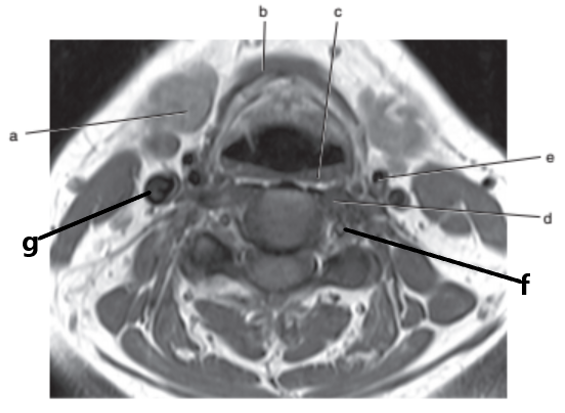

What anatomy is letter e ?

Nasopharynx

What imaging plane is this ?

transverse

What anatomy is letter b ?

Epiglottis

Soft palate